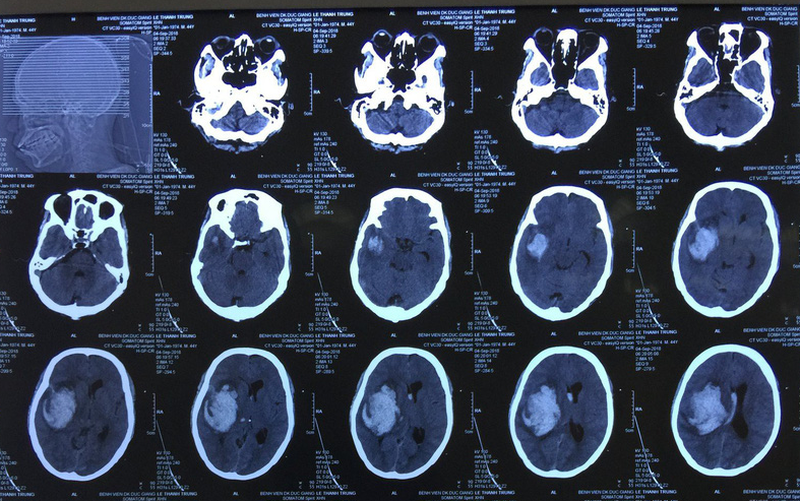

Thời gian chụp CT bao lâu? Khi nào nhận được kết quả? 1 Dựa vào hình ảnh từ chụp CT, bác sĩ biết được chính xác mức độ tổn thương ở từng cơ quan

Kỹ thuật sử dụng máy chụp CT có phát ra những chùm tia X quét qua cơ thể gọi là chụp CT. Khi kết hợp với máy tính sẽ đem lại những hình ảnh 2D hay 3D nhằm xác định tình trạng của các cơ quan trong cơ thể. Dựa vào hình ảnh ghi được, bác sĩ cũng có thể biết được chính xác mức độ tổn thương ở từng cơ quan, dù là nhỏ nhất.

• Chẩn đoán các vấn đề ở não.